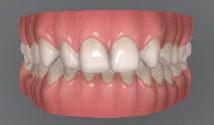

Пациентът постъпи в клиниката с молба за тотална рехабилитация на усмивката. Той не харесваше централ ните си резци, които според него бяха твърде къси и квадратни. Имаше раз стояние от медиално и дистално на латералните му резци. Друго сериоз но оплакване бе свързано с металоке рамичната корона на зъб 12, която бе жълтеникава и неестетична, като цяло не харесваше вида на венците си и както самият той се изразяваше, „вижда се прекалено много от венците при усмивка“.

След диагностиката бяха направени екстра- и интраорални снимки, както и рентгенографии; професионалното почистване бе от изключителна важ ност, бяха дадени и инструкции за лич на орална хигиена. Бе направено интра орално сканиране с Medit i500. Цялата тази информация бе използ вана в приложението Smilecloud за 2D биометричен дизайн. В приложението са налични естест вени форми на зъбите и щом бяха под брани зъби и бе направен дизайн

библиотеката на Exocad. Струва си да се отбележи, че 2D дизайнът от Smile Cloud бе спазен до последния детайл в Exocad smile creator с цел да се създаде 3D obj файл със зъбните форми. След като естетичният дизайн бе готов в model creator модула на Exocad, адитивен 3D мок-ъп модел бе експорти ран и принтиран от принтер Formlabs 3. Моделът бе използван за направата на силиконов водач, за да се изготви мо тивационен мок-ъп в устата на паци ента и да се оценят естетичните па раметри. След като пациентът одобри вида на усмивката си, мок-ъпът бе използван за финализиране дизайна на усмивка та. Мок-ъпът бе използван също така като водач по време на мекотъканна та хирургия, както и при препарация на зъбите.

Препарираните зъби бяха импорти рани в Exocad и насложени върху ес тествените форми от биометричния дизайн, като така стана ясно дали зъ бите са били препарирани коректно. По този начин зъболекарят и зъботехни кът работят в една и съща екосистема и резултатът е оптимален. С короната се справихме чрез диги тална редукция на циркония в Exocad, като по този начин на практика създа дохме циркониево кепе, след което про изведохме фасета от IPS Empress Cad Multi. Кепето от Katana Zirconia на зъб 12 с букално послойно нанесена керами ка бе фрезовано (послойното нанасяне бе направено, за да се подобри връзката и да се осигури адхезивно циментиране на фасетата към циркониевото кепе, както и за да се напасне цветът към този на съседните зъби). При първото сканиране регистрирах ме цялата горна зъбна дъга, така че, ко гато се наложи да сканираме повторно, бе изтрит и сканиран наново само зъб 12, тъй като венците не бяха отдръп нати при второто сканиране.

Една седмица след препарацията на зъбите и циментирането на цирко ниевото кепе бяха изработени 12 IPS Empress Cad Multi фасети. Макро- и микротекстурата на фасе тите бяха направени на ръка, след кое то бяха нанесени 3D характеризации с боички, а полирането отново бе напра вено ръчно, за да им се придаде естест вен и естетичен вид. Предизвикателството тук беше короната да има същите оптични характеристики като тези на остана лите зъби при естествена светлина, през поляризационен и флуоресцентен филтър. 3D принтерът бе Fromlabs, софтуерът за фрезоване – Mill Box, а фрез апаратът –imes icore CORiTEC 350i. В крайна сметка постигнахме ес тествен вид на усмивката с натурал на зъбна морфология при изцяло диги тален протокол, при който дизайнът бе направен първоначално и през всич ки етапи на лечението се придържахме към него до самия край Излишно е да отбелязваме, че всички сме удовлетворени от постигнатото! Преди След Победител в категория „Клиничен случай с изцяло дигитален протокол“ в конкурса „Усмивка на годината 2022“